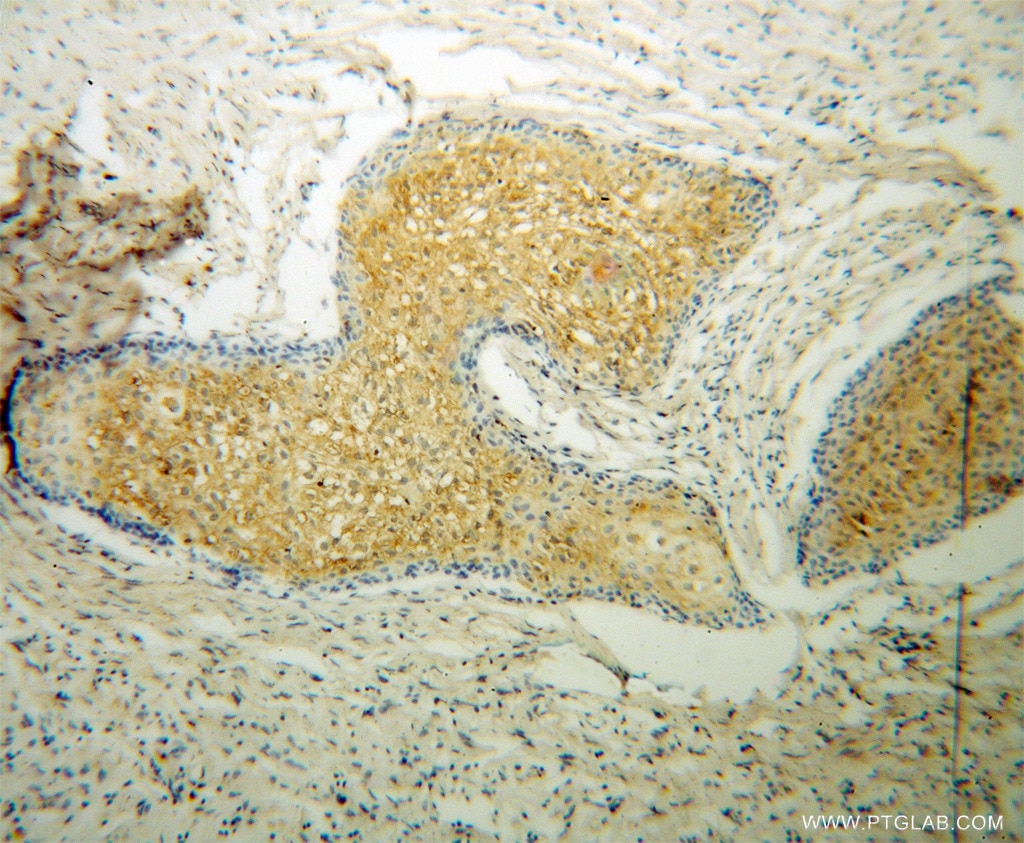

| Positive IHC detected in | human osteosarcoma tissue Note: suggested antigen retrieval with TE buffer pH 9.0; (*) Alternatively, antigen retrieval may be performed with citrate buffer pH 6.0 |

| Immunohistochemistry (IHC) | IHC : 1:20-1:200 |